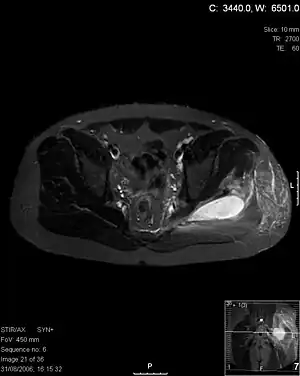

| Transverse T2 magnetic resonance imaging section through the hip region showing abscess collection in a patient with pyomyositis. | |

| Diagnostic method | Diagnostic method used for PM includes ultrasound, CT scan and MRI. Ultrasound can be helpful in showing muscular heterogeneity or a purulent collection but it is not useful during the first stage of the disease. CT scan can confirm the diagnosis before abscesses occur with enlargement of the involved muscles and hypodensity when abscess is present, terogenous attenuation and fluid collection with rim enhancement can be found. MRI is useful to assess PM and determine its localization and extension |